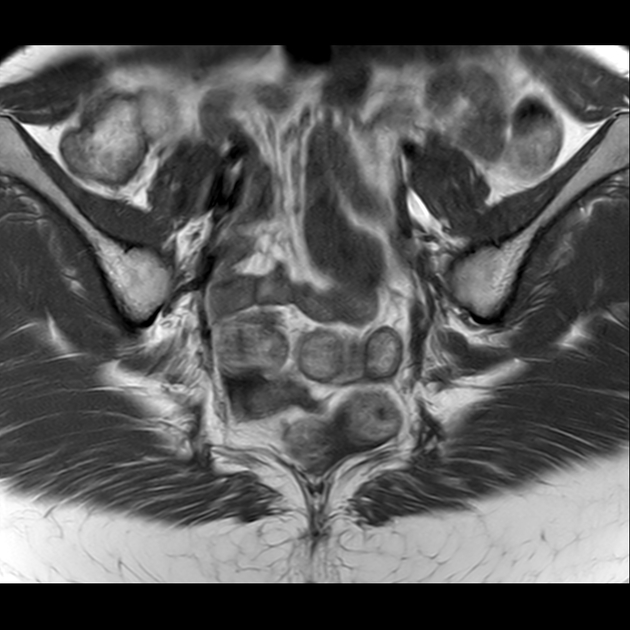

T1

磁共振影像表现